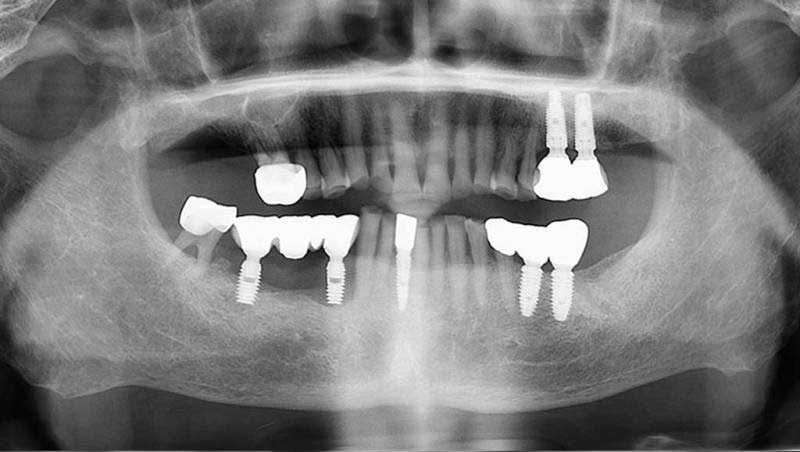

案例1

植牙併發症處理中